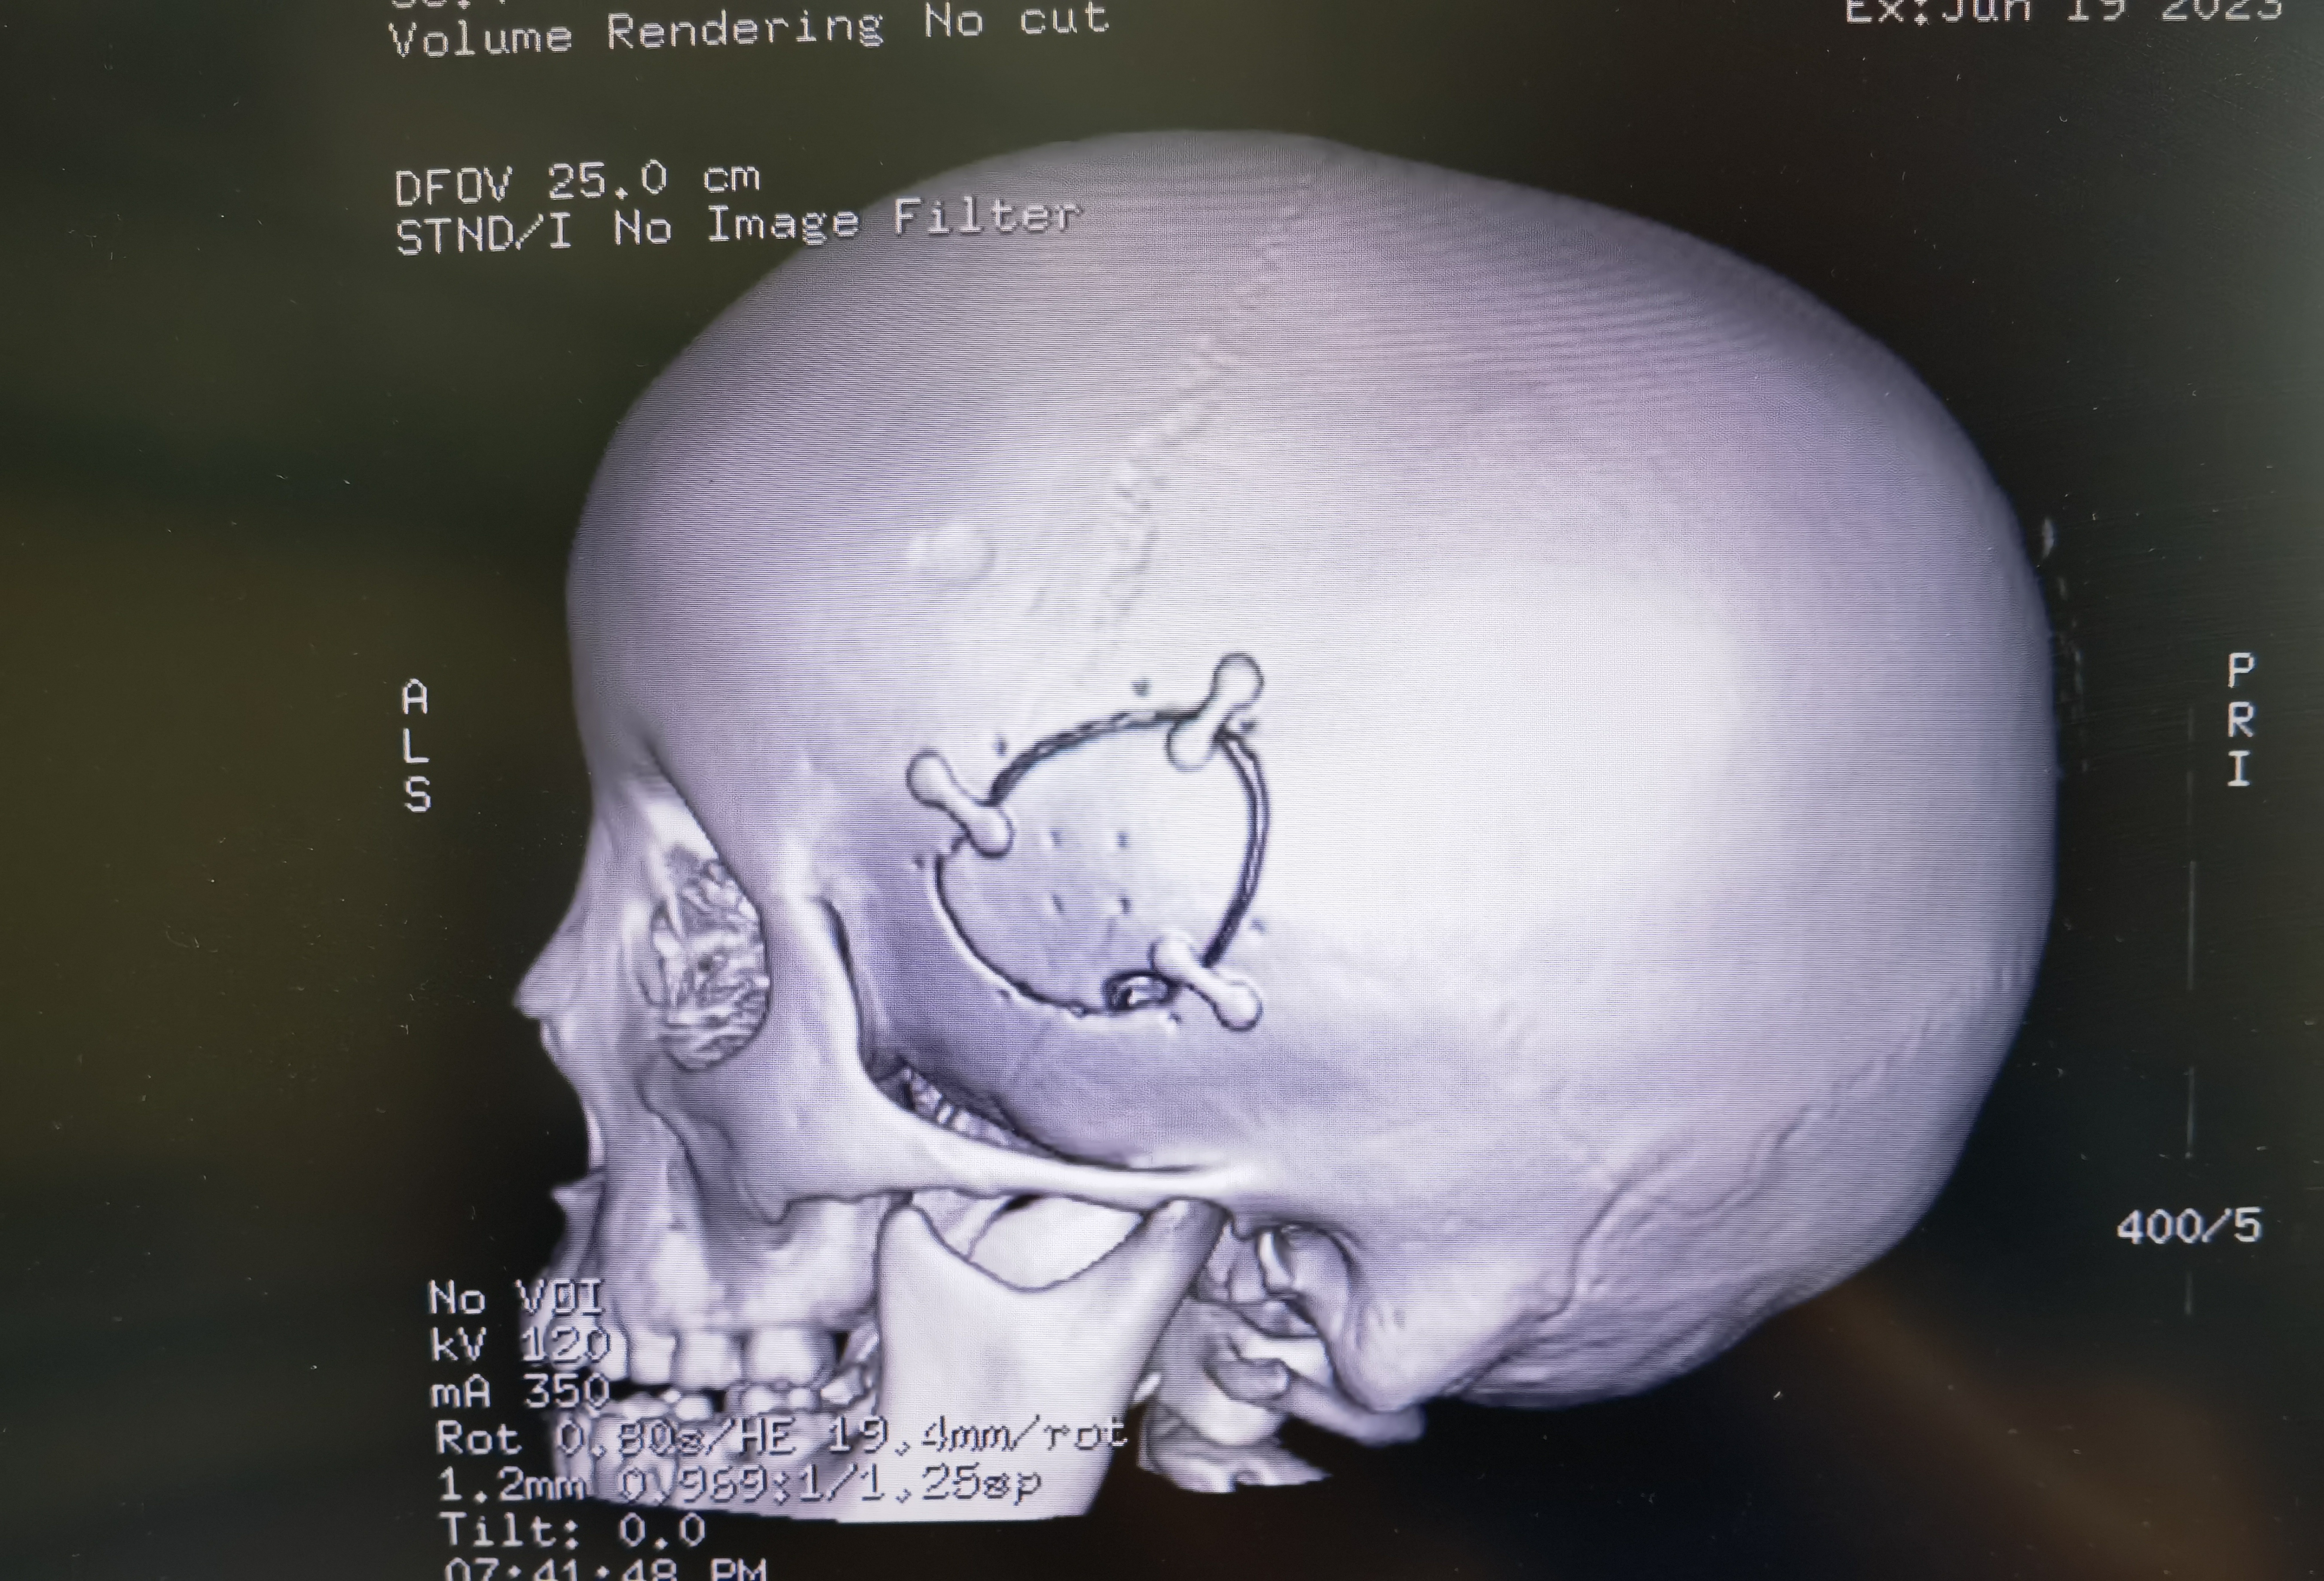

手术切口